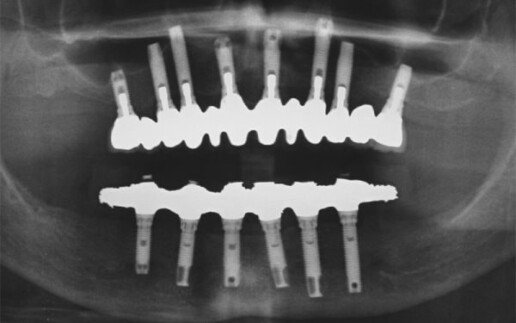

Riabilitazione totale superiore e inferiore su impianti. Gli esiti di una paradontite grave portano alla perdita totale dei denti. E’ necessario ricostruire sia i denti sia i tessuti molli e anche l’osso per il sostegno delle labbra.

Prima

Dopo